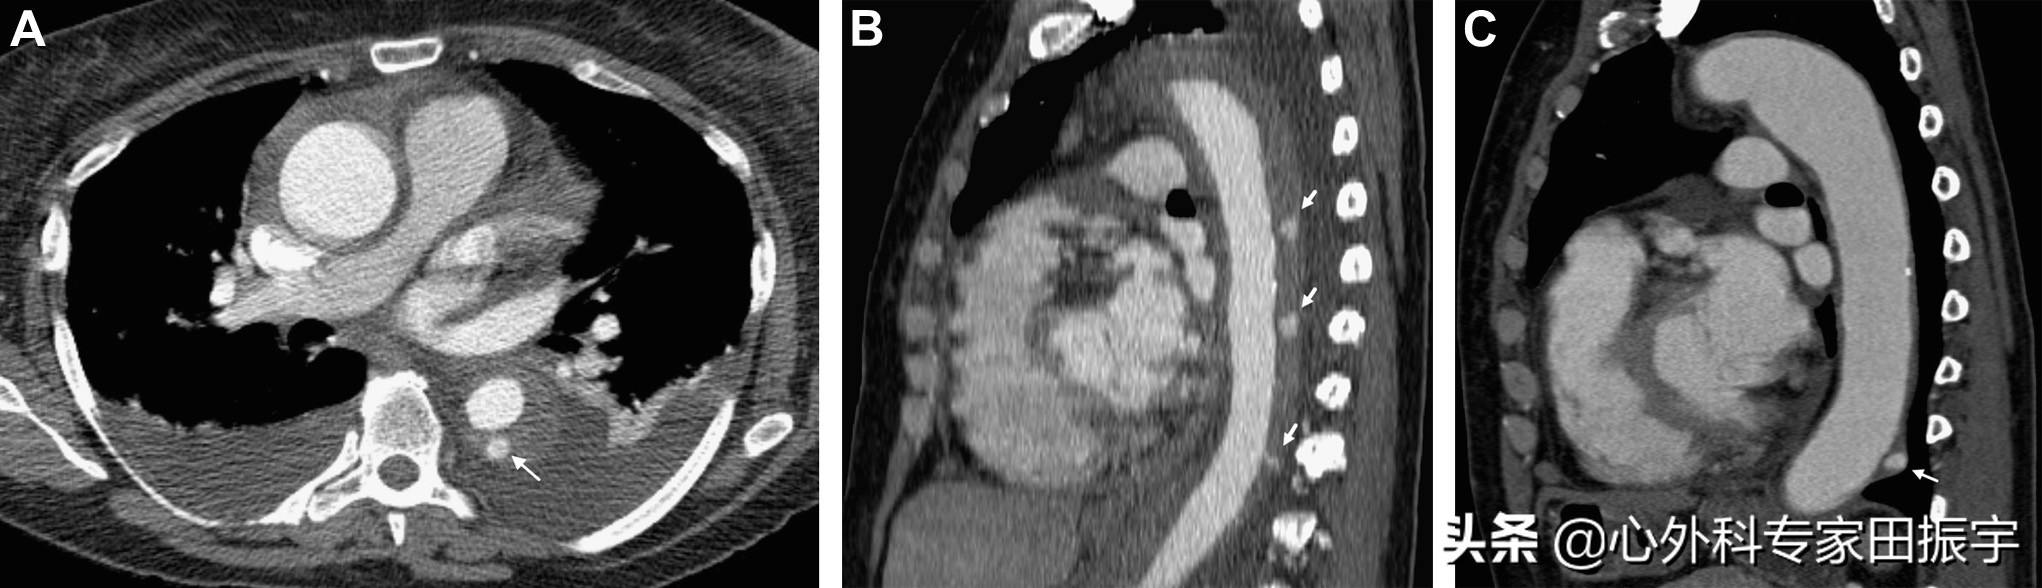

主动脉壁间血肿

图4 一名43岁妇女出现急性背痛和高血压危象。增强CT的轴向(A)和矢状多平面重建(B)CT 图像显示 B 型壁间血肿,血肿厚度为 11 mm(箭头)。3 个月后随访增强CT多平面重建图像(C)和三维体积重建图像(D)显示主主动脉弓远心端发展成假性动脉瘤(箭头)。